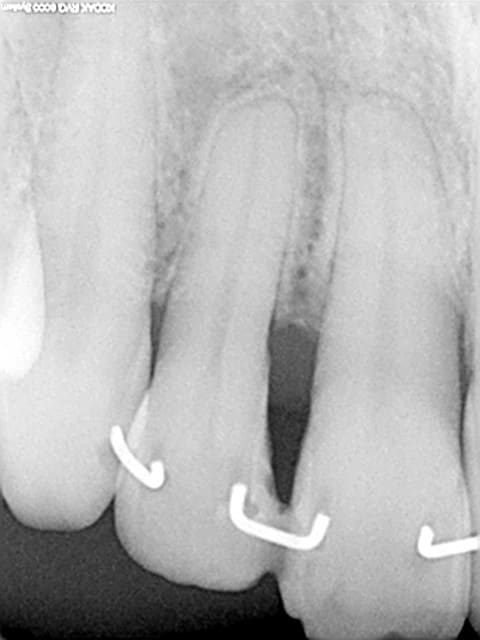

Les attelles d'Abjean j'en pose chaque semaine (ou presque), l'avantage ENOOOOORME par rapport à un "jonc noyé" c'est la rétention 3D que tu n'as pas avec le jonc!

et le délabrement est bcp moindre, en plus quand une attelle lache tu la changes, et pas tout le bastringue!

1) les forêts drill: tu as quelle réf. ???

2) le fil c'est du jonc en 0,8 mm

3) tu fais une gorge horizontale reliant les 2 points de contact jusqu'à la dentine (prof 1 mm) fraise HL 008

4) un léger avant trou à la fraise boule 008 aux extrémités de la gorge (komet H 009)

5) forage basse vitesse prof 1 à 2 mm les puits doivent être le plus parallèle possible (dans le tiers proximal de la dent à distance raisonnable de la pulpe ;-)

6) confection de l'attelle grâce à une pince à bec plat fine modifiée qui te permet de faire toutes les tailles d'entre-axe

7) essayage et puis souvent réessayage et scellement ou collage si tu en as.

C'est comme cela que Le Pr José Abjean nous l'a appris...à la fac.

C'est joli, mais je trouve que sur les radio, les trous sont plus prodonds que la contention et je trouve cela invasif vs fil ou contention classique. Pour quelques cas bien précis, ok, mais pas trop fréquente l'indication non ?

Ben si en fait, c'est la seule:

1 a être discontinue (donc refaisable sans tt déposer encore une fois)

2 a avoir une rétention axiale, vestibulo palatine, et disto mésiale (3 axes)

3 assez facile à mettre en oeuvre (par rapport à la manipulation d'un long fil que tu colles d'un bout qu'il faut tenir pour ne pas qu'il bouge :(....

4 délabrement moins important et risque de fracture de la dent bcp moindre (bord incisal par exemple)

5 résultat immédiat esthétique et absence d'interférences occlusales car entièrement incluse dans les puits et sillons réalisés.